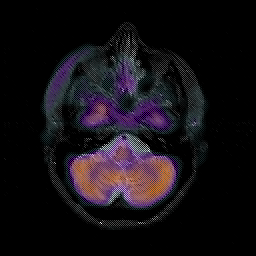

Glioblastoma multiforme overlay -- Slice #13

[Home][Help][Clinical][Tour 1][Tour 2][Tour 3] Slice 13